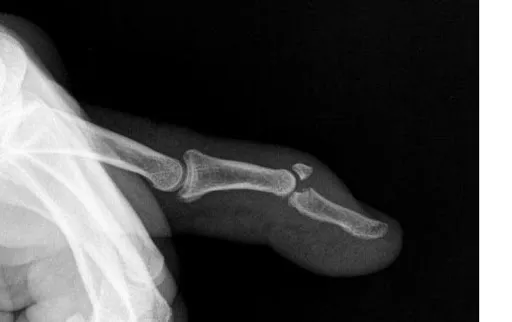

Inmediatamente se dirigió al Sanatorio Austral de Viedma, donde le diagnosticaron Mallet Finger en el dedo anular. En esta afección, el dedo queda en forma de martillo, con imposibilidad de enderezar la punta. Es causada por una lesión en el tendón extensor, que se rompe o arranca un pequeño fragmento óseo. Se realizó una intervención quirúrgica.

La especialista a cargo del caso examinó al trabajador y concluyó que tenía un grado de incapacidad del 7,27%. Determinó la imposibilidad de extender activamente la punta del dedo anular, tal como se había observado el día del accidente.